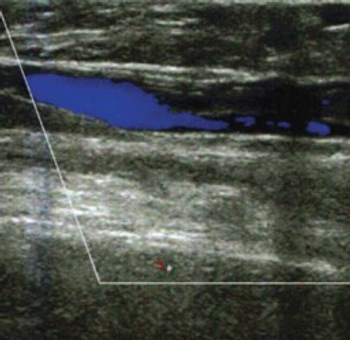

Ultrasound diagnosis of tenosynovitis has now been shown to be superior to clinical signs and symptoms (eg, early morning stiffness, symmetrical arthritis, and hand joint arthritis) in predicting early rheumatoid arthritis.